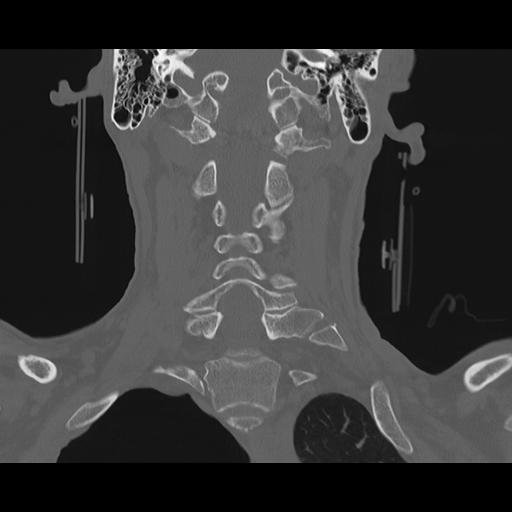

16 HUESO,,Coronal,2.000,HUESO,Coronal,